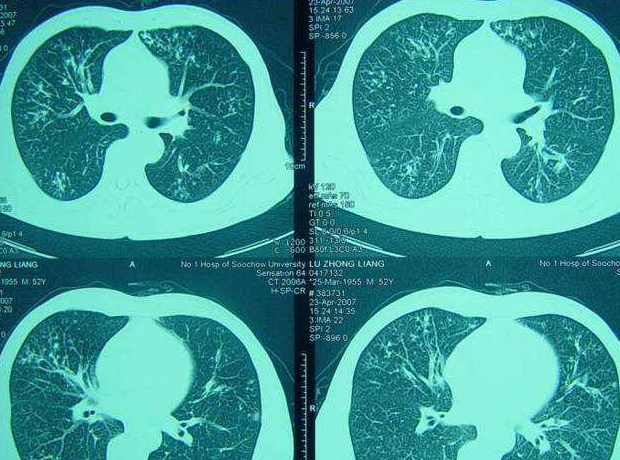

肺癌转移是什么意思?转移性肺癌的症状有哪些?

转移性肺癌意味着患者体内任何地方的恶性肿瘤都以不同的方式转移到患者的肺部。约60%的恶性肿瘤在初次检查时有肿瘤转移,其中30% ~ 50%的肿瘤转移到肺。不同肿瘤的肺转移发生率不同,其中甲状腺癌、乳腺癌、肾癌、绒毛膜癌和骨肉瘤的发生率可达60%以上。肺癌转移的发生率与原发肿瘤的生物学特征和机体免疫功能有关。

此外,转移性肺癌的发生与肿瘤相关信号和基因异常有关。然而,转移性肺癌大多是多种不同大小和密度分布在肺两侧的病变。目前,这些晚期癌症病例没有有效的治疗方法。外科治疗可能被考虑用于只有一个单独的肺转移病灶的少数病例。外科治疗、化疗和放疗是转移性肺癌的三种主要治疗方法。治疗的选择取决于原发肿瘤的状态、转移性肺癌的类型、位置和数量以及患者的总体状况。外科治疗是转移性肺癌的首选治疗方法,也是目前转移性肺癌的标准治疗方法。如果其他部位没有转移,切除肺转移瘤可以达到根治效果。许多肿瘤对化疗或放疗不敏感,如软组织肉瘤的肺转移。手术是一种重要的治疗方法。从经济角度来看,运营成本对效果的比率也更高。然而,最终的选择取决于医生的指导。